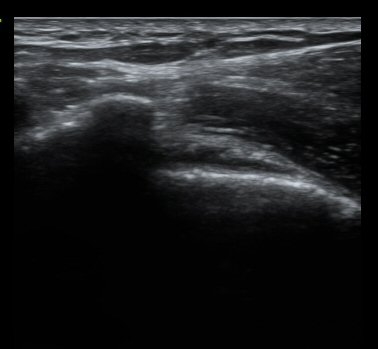

ȸÀü±Ù°³°£°Ý Ⱦ´Ü¸é°Ë»ç¿¡¼­ Á¡¾×³¶³» ¼ö¾×Àú·ù°¡ °üÂûµÈ´Ù(±×¸² 1). ÀÌµÎ¹Ú±Ù°Ç °í¶û¿¡¼­´Â ƯÀÌ ¼Ò°ßÀ» º¸ÀÌÁö ¾Ê´Â´Ù(±×¸² 2). ȸÀü±Ù°³°£°Ý ³»Ãø¿¡¼­ °ß°©ÇϱٰÇÀÇ ÆÄ¿­°ú Á¡¾×³¶³» ¼ö¾×Àú·ù°¡ °üÂûµÈ´Ù(±×¸² 3, 4). ±Ø»ó°Ç Ⱦ´Ü